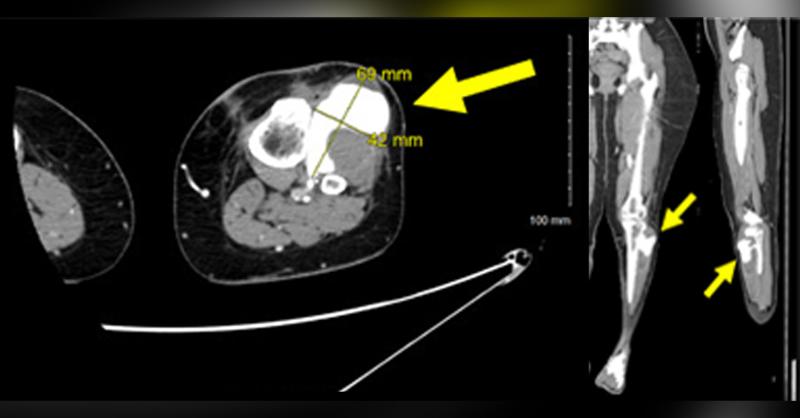

- Pseudoaneurysm in the Anterior Tibial Artery after Arthroscopic Anterior Cruciate Ligament Repair: A Case Study

One of the most frequently researched injuries in the orthopedic literature is anterior cruciate ligament (ACL) tears. Although the prevalence of ACL tears in the general population has not been precisely determined, it has been estimated to range from 30 to 78 per 100,000 individuals (1). Arterial pseudoaneurysms, which account for less than 0.3 p